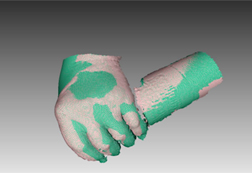

以下は、Space Spiderで取得したデータの画像です。特に部品のエッジ部分を高密度で繊細に表現できるようになりました。

特集 ハンディ3Dスキャナーをリハビリで利用する

1. 従来のマニュアル測定方法に代え、非接触ハンディ3Dスキャナーで関節の曲がり状態を調べる。

2. 手の”むくみ”を診断する。むくみ・ある/なしの状態を1ミリ精度で表現する。

3. 手の状態を3Dで調べる。体積や図面も作成できる。計測時間は数秒間。